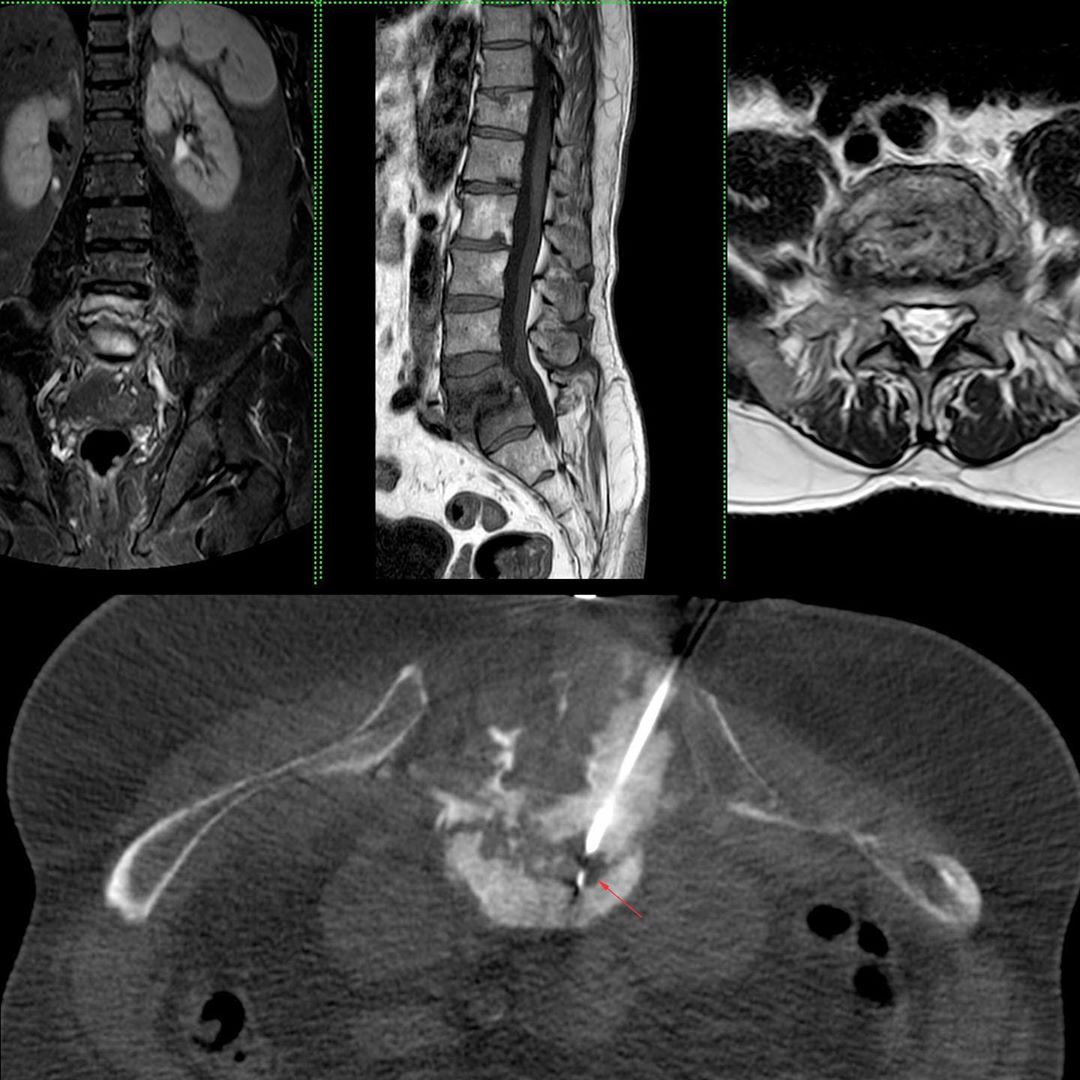

This is a 60-years old man with backache. MRI showed infectious spondylitis at L5/S1. The presumptive diagnosis was tuberculosis.

Instead of starting anti-TB treatment, which is often the norm, the patient was sent for a CT guided biopsy to confirm the diagnosis and to obtain material for culture, sensitivity, etc.

The biopsy was performed using an 18G core biopsy needle introduced through an 11G bone biopsy needle under sedation using an oblique transpedicular route into the disc and end-plate. Acinetobactor was cultured and the patient was treated with appropriate antibiotics.